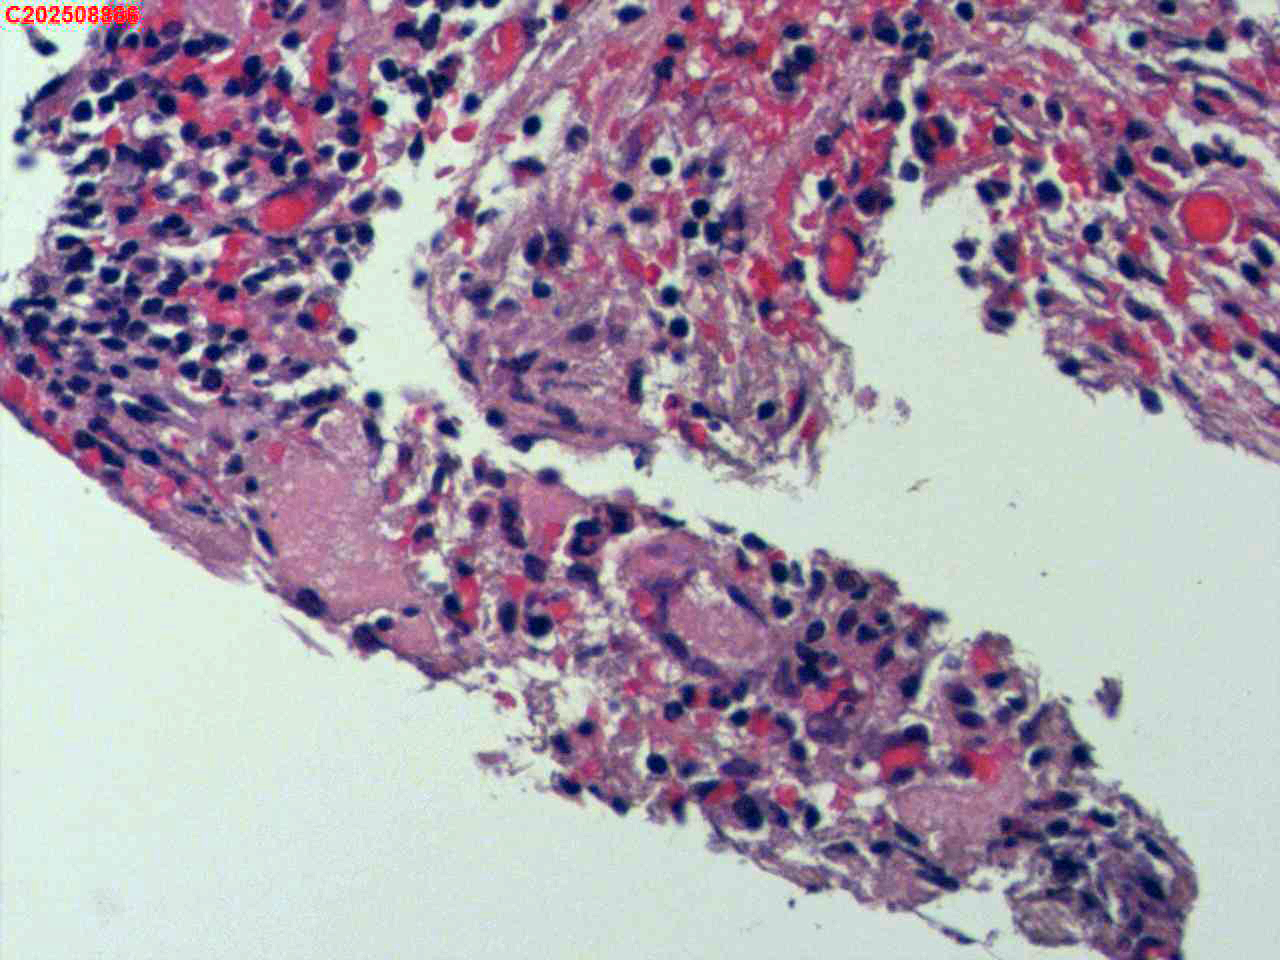

纤支镜咬检

肺TB?Ca?

胸部CT(平扫):考虑双肺感染性病变,结核?支气管炎?请结合临床及其它检查。

标本名称

右肺上叶后段开口咬检组织

大体所见

右肺上叶后段开口处粘膜不规则增生。

肉芽肿性炎的可能性大些!

有坏死,深染变形的细胞需要排一排神经内分泌肿瘤。